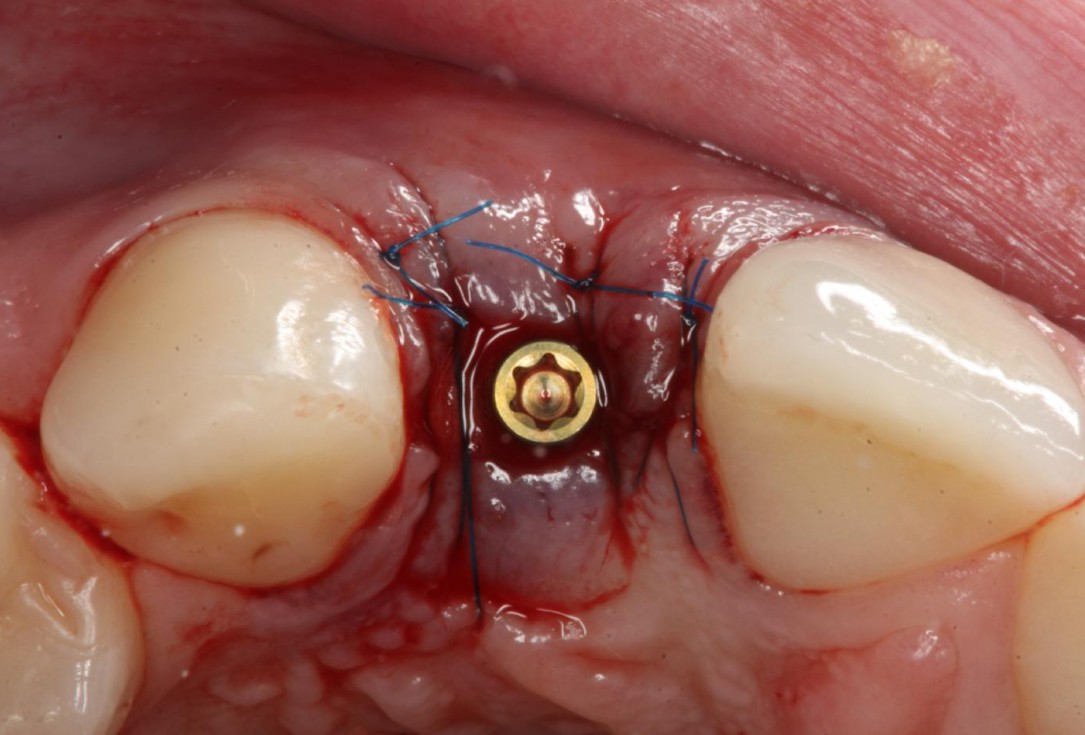

7/12 - Tension-free wound closure, occlusal viewSoft tissue thickening at immediate implant placement and GBR with mucoderm® and maxgraft® - Dr. A. Puisys